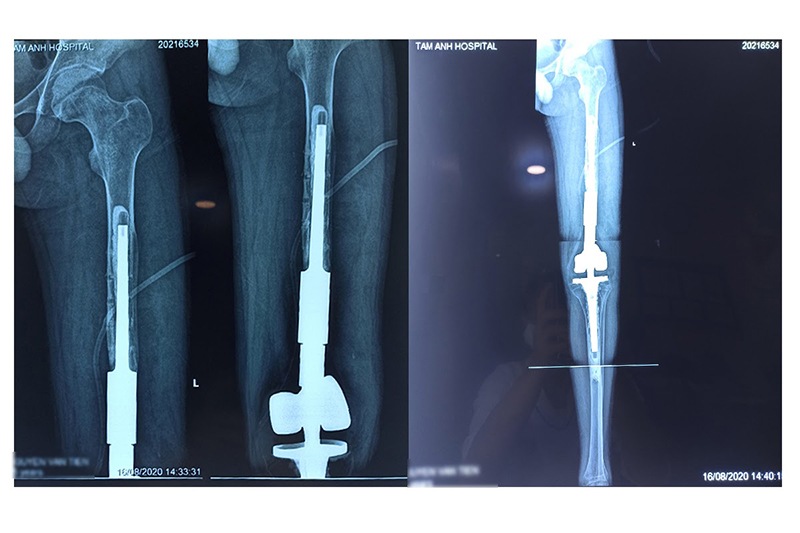

Ngày 13/8/2020, Bệnh viện Đa khoa Tâm Anh, Hà Nội vừa phẫu thuật thành công ca thay khớp và cấy ghép xương chân cho bệnh nhân ung thư xương. Đây là ca phẫu thuật cực kỳ phức tạp thay thế phần xương cũ, tạo hình khớp, chuyển vạt che phủ, bảo tồn nguyên vẹn phần chân bị tổn thương do ung thư bằng phương pháp thay khớp nhân tạo kèm ghép đoạn xương chế tạo từ vật liệu kim loại Titan với công nghệ in 3D hiện đại.

PGS.TS.BS Trần Trung Dũng, người trực tiếp thực hiện ca phẫu thuật thay khớp gối và ghép xương cho bệnh nhân T., cho biết: ‘’Phần xương đã mất của bệnh nhân khoảng 20cm, với khớp nhân tạo truyền thống thì không thể đáp ứng được cho những trường hợp này. Vì vậy chúng tôi đã sử dụng khớp chuyên dụng dành riêng cho các trường hợp ung thư, bệnh nhân được thay toàn bộ khớp gối và một phần xương đùi.’’

Đối với những bệnh nhi tuổi thiếu niên đang tuổi phát triển chi thể, do đó bài toán khó với bác sĩ là tạo sự cân bằng chiều dài hai chân sau khi thay xương khớp nhân tạo. Trong trường hợp của cháu T., sau lần điều trị 2 năm trước, 2 chân cháu bị chênh lệch tới 5cm. Sau ca phẫu thuật tại BVĐK Tâm Anh, khoảng chênh lệch giữa hai chân giảm xuống còn dưới 3cm.

Nhận định đây là một ca phẫu thuật phức tạp, đầy khó khăn, để đảm bảo chức năng của xương chân và khớp gối, ekip phẫu thuật đã sử dụng khớp nhân tạo kèm ghép xương từ vật liệu kim loại Titan để cấy ghép thay phần xương giả đã bị gãy, tạo độ vững cho xương chân, giúp bệnh nhân có thể đi lại bình thường mà không cần nạng hỗ trợ.

Trường hợp của bệnh nhi T., vì phần xương nhân tạo trước đó không liền, khớp gối không thể gập duỗi, bác sĩ quyết định sử dụng phần khớp và xương từ vật liệu kim loại Titan để thay thế phần xương cũ, bảo tồn toàn bộ chi thể cho bệnh nhân và tránh nguy cơ cắt cụt chi thể. Với phần xương từ kim loại Titan đặc biệt được thiết kế riêng phù hợp với cấu trúc của đoạn xương nhân tạo, giúp cho phần xương được cấy ghép liên kết chặt chẽ, bảo đảm khả năng chịu lực và truyền tải lực. Kết hợp với công nghệ in 3D tại BVĐK Tâm Anh, vật liệu kim loại có thể được chế tạo với mọi hình dạng và kích thước theo yêu cầu, đảm bảo được về mặt kỹ thuật của cuộc phẫu thuật.